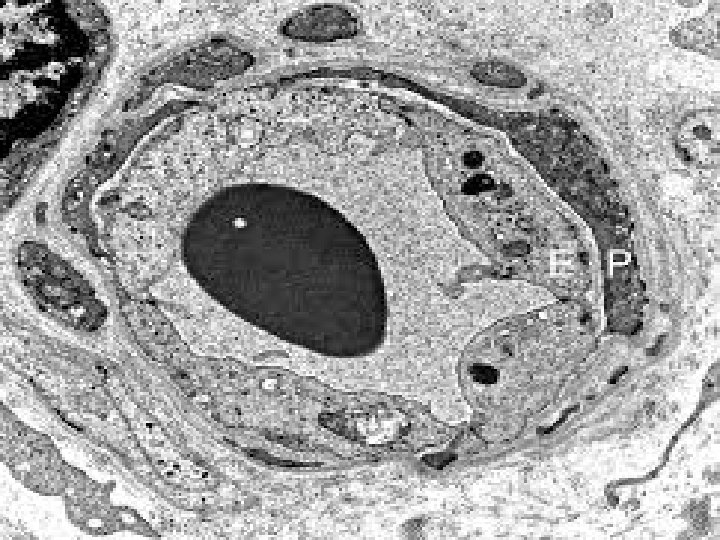

Les capillaires continus

Les capillaires en microscopie électronique � Les capillaires continus � Les capillaires fenêtrés � Les capillaires discontinus (sinusoïdes)